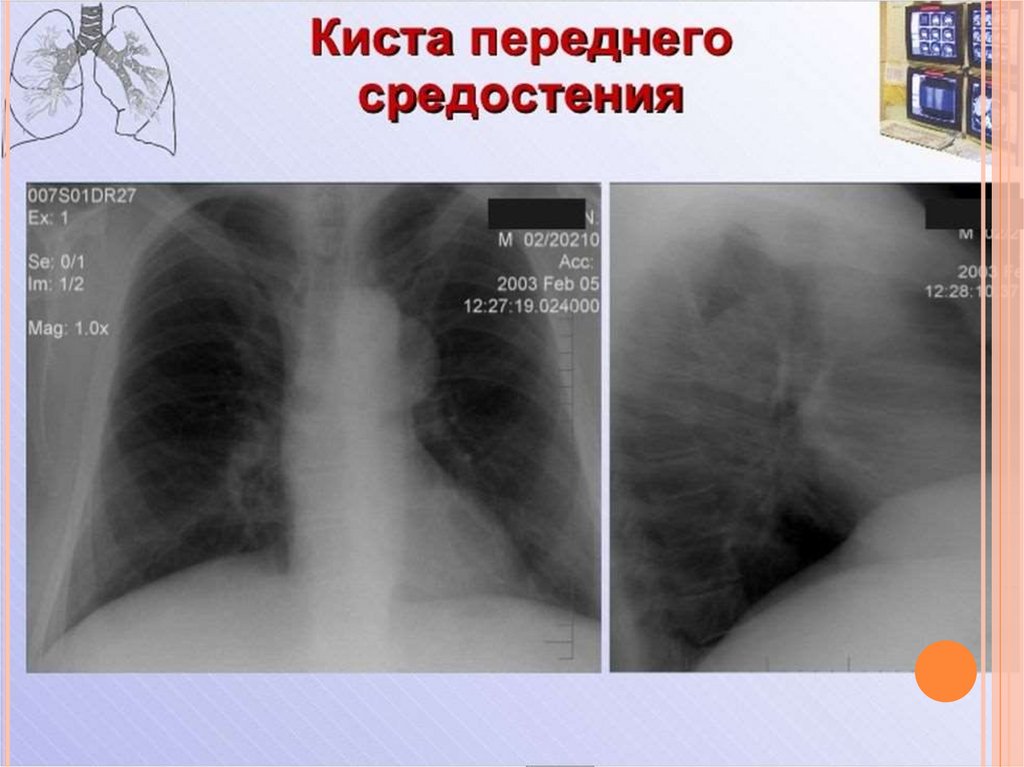

Рентгеновские снимки тератомы средостения: Диагностика и лечение

Раздел: Фотоэссе